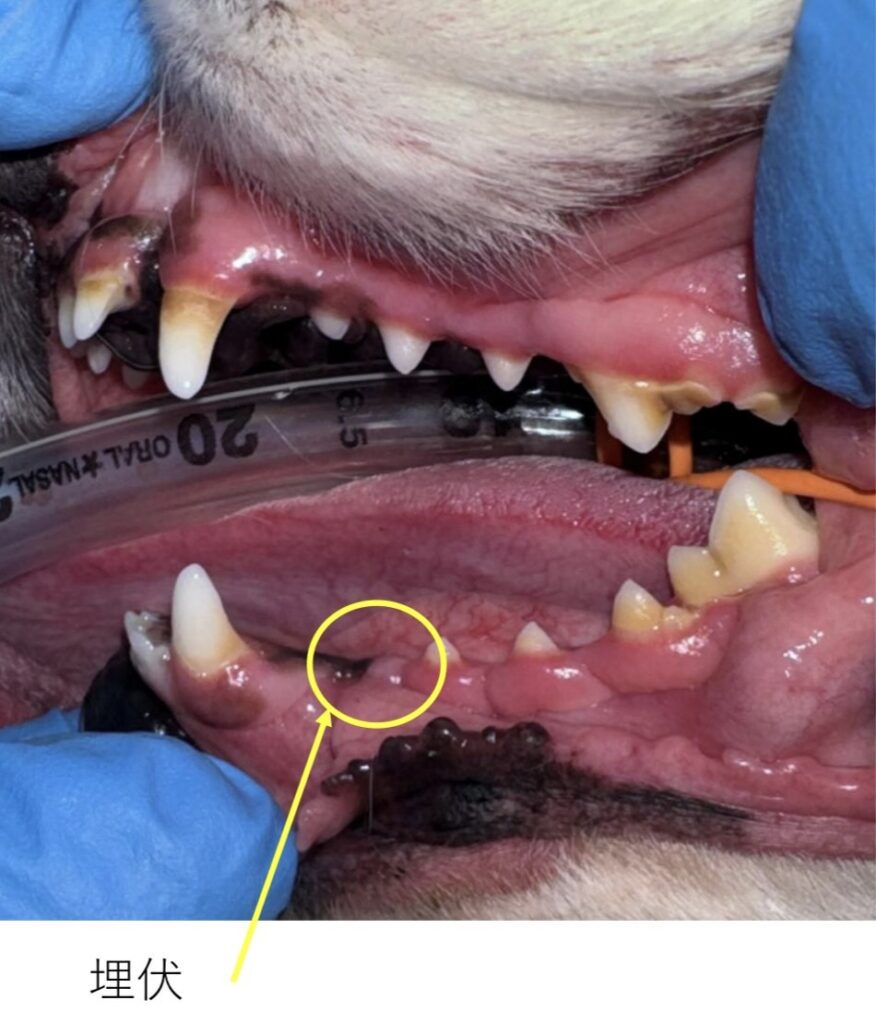

・埋伏歯

が認められました。

全体的に角化歯肉の肥厚が認められ、歯冠歯肉に埋没していました。

また、左下顎第一前臼歯は歯肉内に埋伏していました。

埋伏歯含歯性嚢胞(※詳しくは下へ👇)の発生リスクを伴うため、歯冠露出を目的として歯肉切開を行いました。